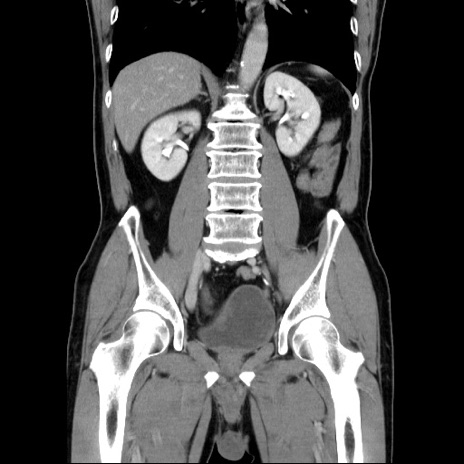

症例34(冠状断像)

【症例】60歳代 男性

【主訴】右鼠径部膨隆

【現病歴】1年程前より右鼠径部膨隆あり。自己にて還納可能だったため放置していた。3時間前より右鼠径部の脱出を認め、還納困難となり受診。

【既往歴】高血圧

【身体所見】右鼠径部に小児頭大の膨隆あり。弾性硬であり、用手還納は困難。左鼠径部にも膨隆を認める。脱出はなし。